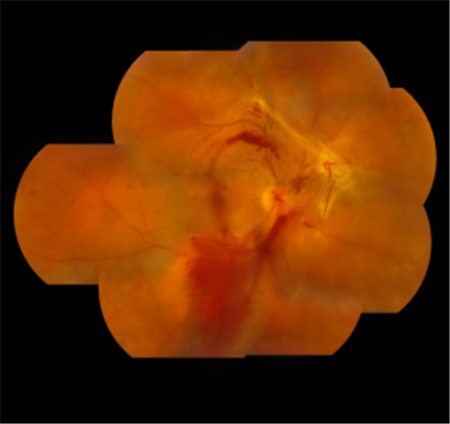

糖尿病患者如果沒(méi)有將血糖控制好,長(zhǎng)期血糖偏高會(huì)損傷血管內(nèi)皮細(xì)胞,而我們的視網(wǎng)膜上布滿大量的微絲血管,這些血管也會(huì)受到影響,從而引發(fā)一系列的視網(wǎng)膜病變,如視網(wǎng)膜新生血管、微血管瘤、糖尿黃斑水腫和視網(wǎng)膜脫離等。糖尿病視網(wǎng)膜病變主要有三種形式,可嚴(yán)重影響視力:

1、眼內(nèi)出血:新生血管破裂導(dǎo)致的眼內(nèi)出血,又稱為玻璃體出血。出血狀態(tài)下的玻璃體是混濁的,所以我們?cè)诳礀|西時(shí),光線無(wú)法正常到達(dá)視網(wǎng)膜,視力也會(huì)受到影響。

3、視網(wǎng)膜脫離:眼內(nèi)反復(fù)出血會(huì)引起瘢痕化,進(jìn)而造成視網(wǎng)膜變形,嚴(yán)重可致視網(wǎng)膜發(fā)生脫離。